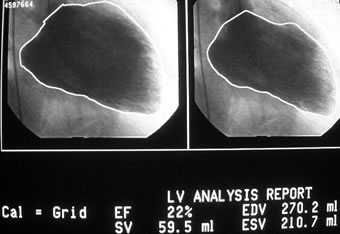

HOT ! 心筋梗塞の合併症 : 画像診断アトラス 心筋梗塞の合併症 画像診断アトラス DVD付き | 吉川 純一, 阿部

心筋梗塞の合併症 : 画像診断アトラス 心筋梗塞の合併症 画像診断アトラス DVD付き | 吉川 純一, 阿部の詳細情報

心筋梗塞の合併症 画像診断アトラス DVD付き | 吉川 純一, 阿部。071:心筋梗塞合併症(2) 冠動脈疾患(22)(望月吉彦先生。京都市東山区の内科・循環器内科ならいとう内科クリニック|狭心。「心筋梗塞の合併症 : 画像診断アトラス」Hutchison Stuart J / 吉川 純一 / 阿部 幸雄定価: ¥ 13000#HutchisonStuartJ #Hutchison_Stuart_J #吉川純一 #吉川_純一 #阿部幸雄 #阿部_幸雄 #本 #自然/医療・薬学・健康以前いただいたものになりますが、ほぼ使用せずにいたので出品することにしました。確認できるところでマーカーや書き込みはありません。。4.心筋梗塞・心筋症 | 日本メジフィジックス株式会社。Kaiのチャクラケアブック しおり•ポスター付

• 心筋梗塞の合併症 画像診断アトラス DVD付き | 吉川 純一, 阿部